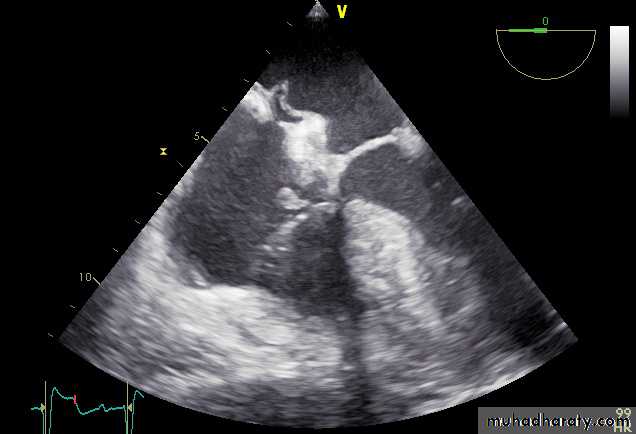

Vegatations on the aortic valve

35

VEGETATIONS

36

37

38

39

40